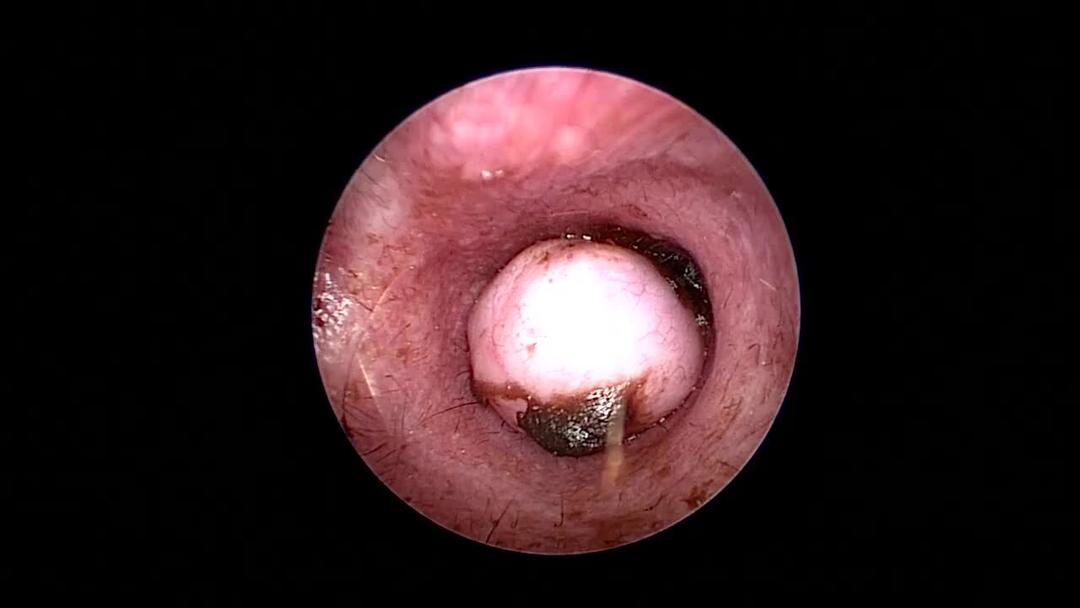

Otoscopic examination, ceruminous adenoma, dog

By use of an otoscope, a flesh-colored, smooth mass is visualized in the horizontal ear canal of a dog with a small amount of ceruminous debris around it. The mass was diagnosed as a ceruminous adenoma.

Courtesy of Dr. Jason Pieper.